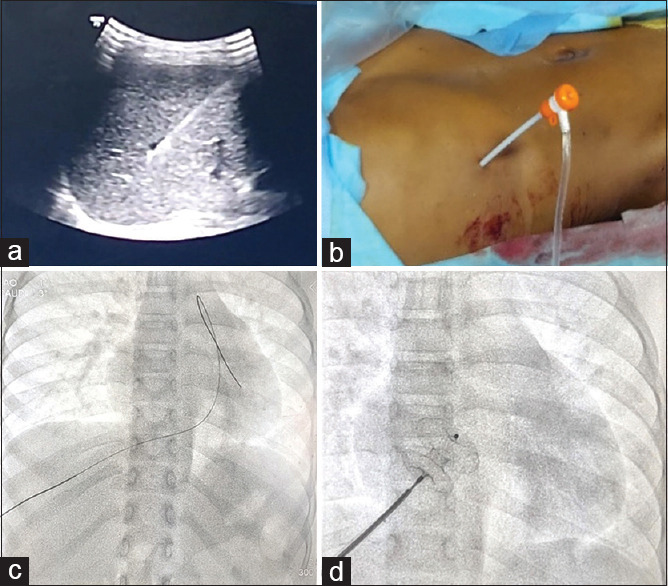

Abstract: Routes for transcatheter closure of ostium secundum atrial septal defect (OS ASD) by device implantation include hepatic vein & jugular vein besides standard transfemoral approach. We report the case of a female child with OS ASD, who presented with an anomalous systemic venous drainage. Only the hepatic vein was draining directly to RA hence the only option left was transhepatic. Multidisciplinary consensus was taken and the procedure proceeded under general anaesthesia. To avoid cathlab misadventures, tracing systemic venous drainage besides pulmonary venous drainage in a case of OS ASD is important. The anaesthetist should be aware of the transhepatic approach and possible complications which may arise. Preparedness for the complications and invasive monitoring ensures success for this challenging procedure.